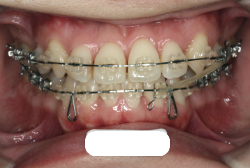

凸凹な歯並びのことを叢生といいます。矯正歯科に来院する患者様の主訴の中で、最も多いのが「配列の凸凹を真っ直ぐにしたい」というものです。歯の大きさと顎の大きさの調和がとれていないことが原因です。

凸凹を主体としたケースの場合、当院の平均治療期間は18ヶ月ですので、このケースは少し長めに経過しました。理由の一つは凸凹の程度がかなり重症だったと言うことですが、もう一つは、右下第2大臼歯が45度くらい前傾していたため、それを整直化させるために時間を要したと考えています。いずれにしても最終結果は大変よい状態と思います。

治療前は並びが乱れて見た目が悪いというのはもちろん問題ですが、歯科医学的に一番困るのは噛み合わせが悪いという点です。上下の犬歯(3番目の歯)は、上下的に離れた位置にあるため接触することができません。つまり歯としては存在していても、歯としては機能していないということです。